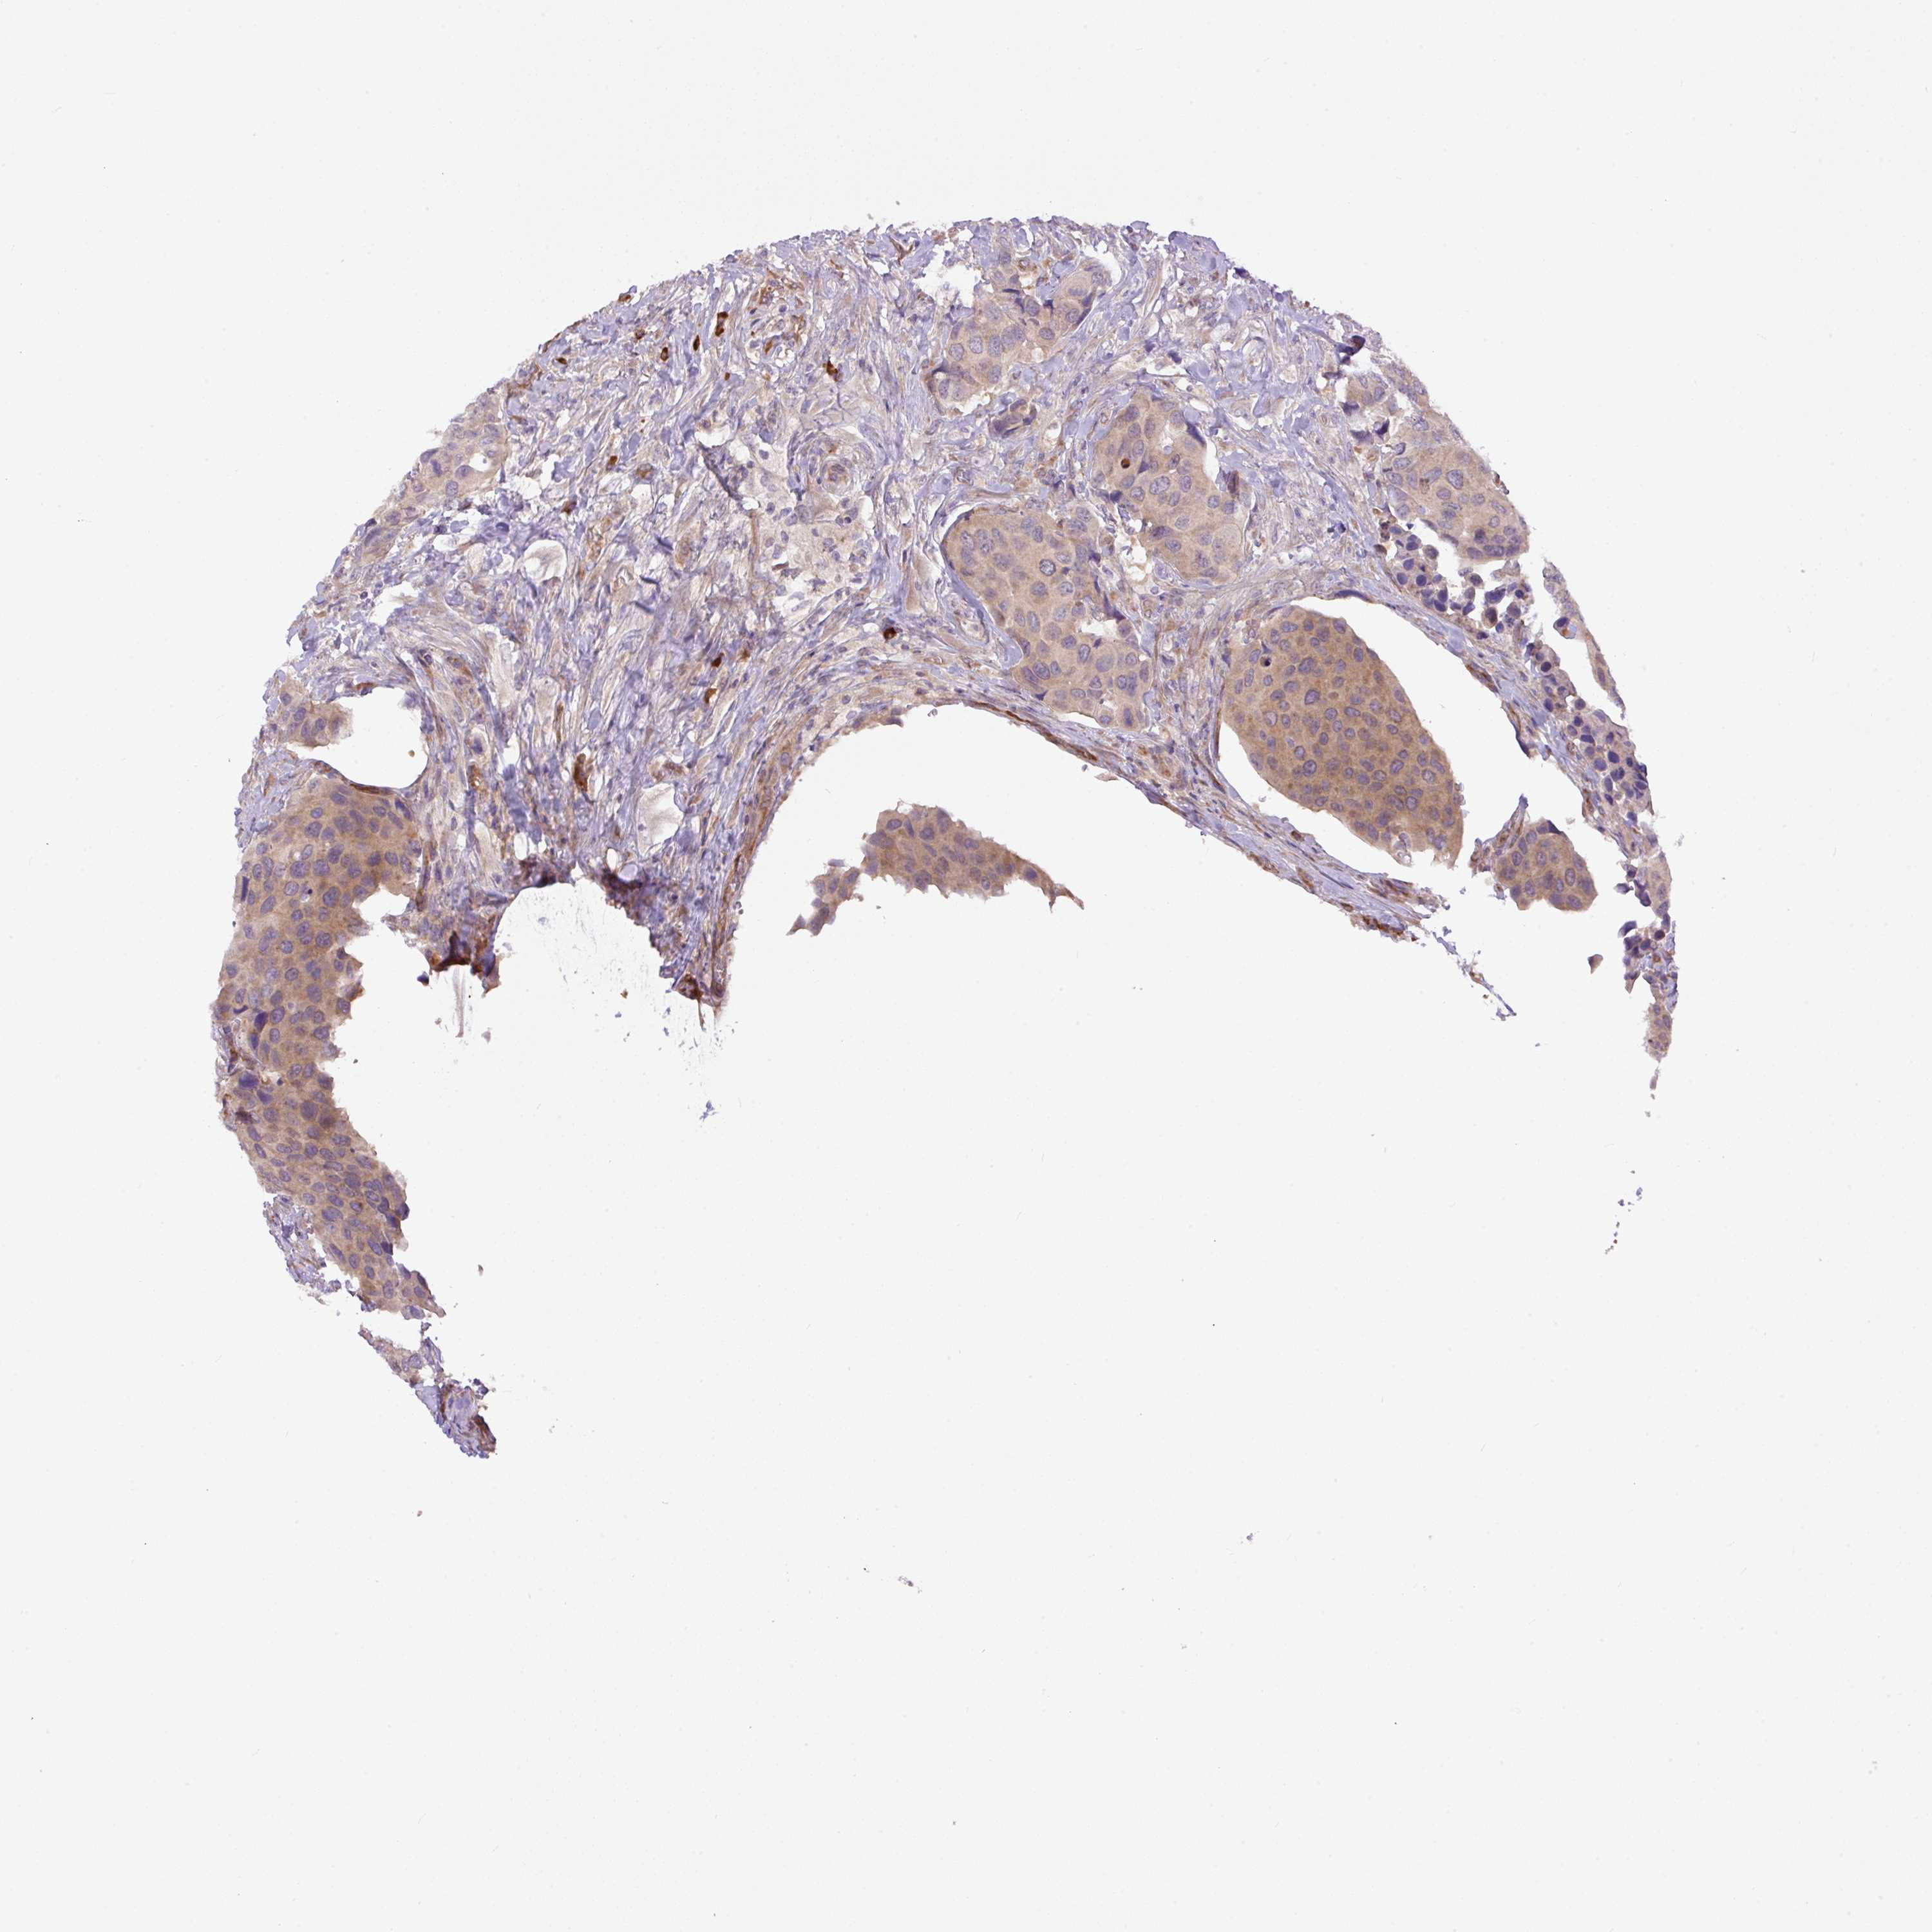

UROTHELIAL CANCER - Protein expressioni

A mouse-over function shows sample information and annotation data. Click on an image to view it in a full screen mode. Samples can be filtered based on level of antibody staining by selecting one or several of the following categories: high, medium, low and not detected. The assay and annotation is described here.

Note that samples used for immunohistochemistry by the Human Protein Atlas do not correspond to samples in the TCGA dataset.

Antibody stainingi

Antibody staining in the annotated cell types in the current human tissue is reported as not detected, low, medium, or high, based on conventional immunohistochemistry profiling in selected tissues. This score is based on the combination of the staining intensity and fraction of stained cells.

Each image is clickable and will lead to virtual microscopy that enables deeper exploration of all samples and also displays staining intensity scores, fraction scores and subcellular localization as well as patient and tissue information for each sample.

Antibody HPA043900

Antibody CAB004541

Staining

High

Medium

Low

Not detected

Intensity

Strong

Moderate

Weak

Negative

Quantity

>75%

75%-25%

<25%

None

Location

Nuclear

Cytoplasmic/membranous

Cytoplasmic/membranous,nuclear

Urothelial carcinoma, High grade

Urothelial carcinoma, Low grade